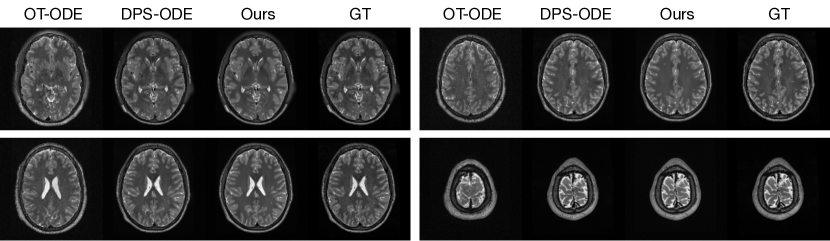

Appendix G Additional Qualitative Results

| OT-ODE DPS-ODE Ours GT | OT-ODE DPS-ODE Ours GT |